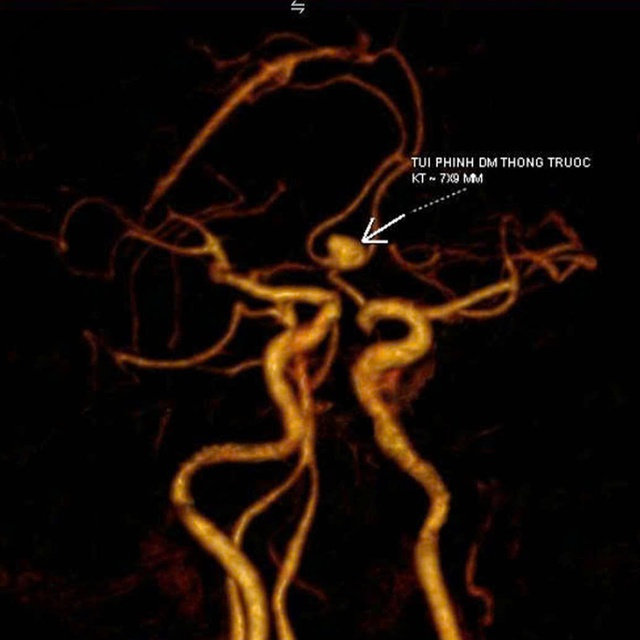

TS.BS Nguyễn Đức Anh (Trưởng khoa Ngoại Thần kinh - Cột sống) chỉ định chụp CT mạch máu não. Kết quả phát hiện túi phình kích thước 7×9mm tại đoạn động mạch thông trước, cổ rộng, vị trí có nguy cơ vỡ rất cao, dễ gây xuất huyết não và đột quỵ nguy hiểm.

Kết quả phát hiện túi phình kích thước 7×9mm tại đoạn động mạch thông trước, cổ rộng, vị trí có nguy cơ vỡ rất cao, dễ gây xuất huyết não và đột quỵ nguy hiểm. (Ảnh: BVCC)